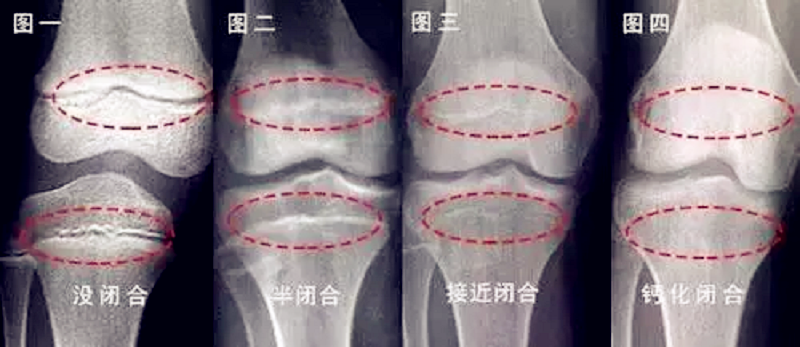

要具体了解孩子的骨骺线是否闭合通常只需要去医院拍一个左手腕关节(16周岁以下)或左侧膝关节(16周岁以上)的正位片。骨骺线没有闭合,长高空间很大,一年每年可长10cm;骨骺线半闭合,生长空间也还有,每年大概可以长6-7cm;骨骺线接近闭合,生长速度开始减慢,每年大概长1-3cm;骨骺线完全闭合,则没有长高空间,身高停止增长。因此,孩子要增高,一定要赶在骨骺线闭合前。